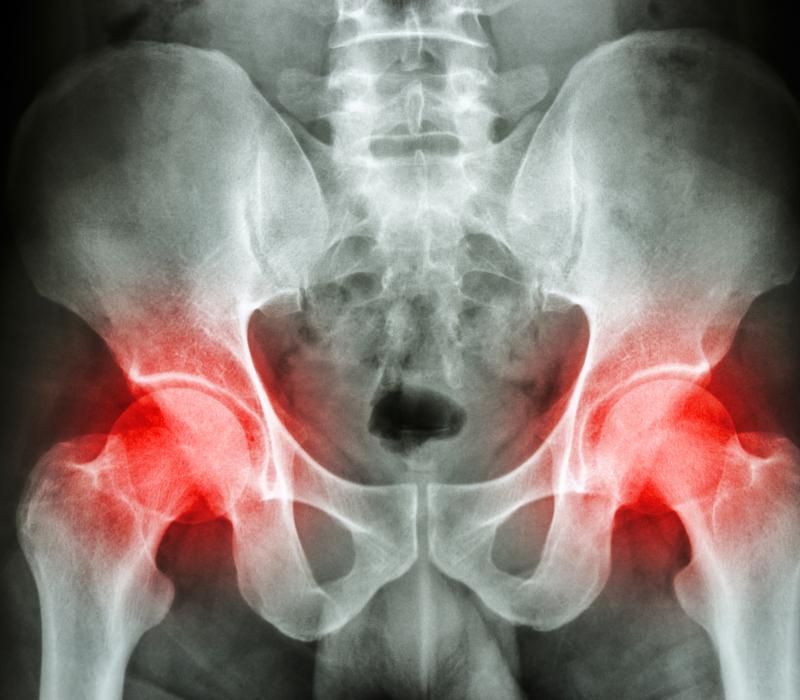

30-Reumatoide.

Reumatoïde artritis, osteoartritis & jicht

• Osteoartritis

• Reumatoïde artritis

• Jicht